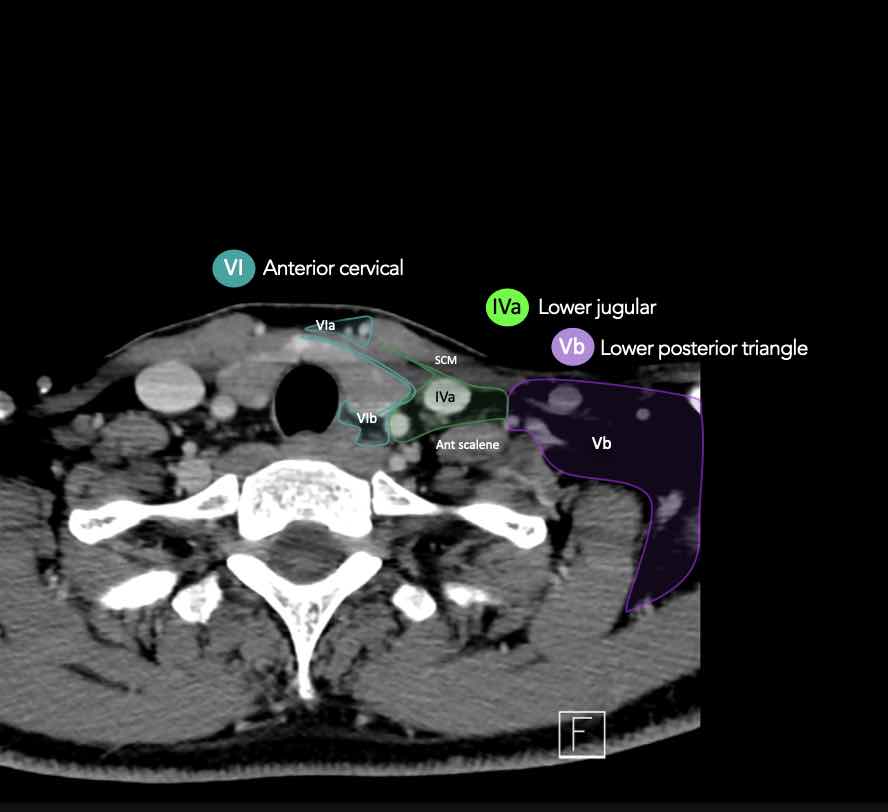

CT Scan Mặt Cắt Ngang (Axial CT)

Các lát cắt CT mặt phẳng ngang tương ứng với hình minh họa tổng quan.

Các lát cắt CT mặt phẳng ngang với hình ảnh chi tiết hơn.

Nhấp vào hình ảnh để phóng to.

VI – Cổ trước

Tầng này chứa các hạch tĩnh mạch cảnh trước nông (tầng VIa) và các hạch sâu hơn bao gồm hạch trước thanh quản, trước khí quản, cạnh khí quản và hạch thần kinh thanh quản quặt ngược (tầng VIb).